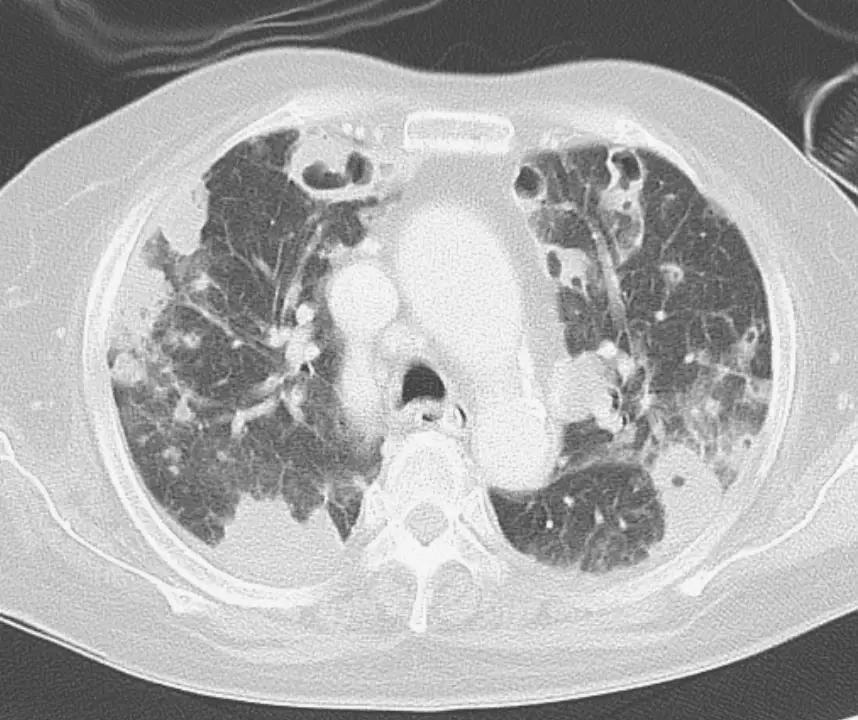

病患胸部X光片與電腦斷層影像如圖, 以下診斷何者最為可能:

從胸部斷層掃描(CT)可見:

- 多發性周邊及靠近胸膜的圓形結節與楔形實變影,包括大小不等的結節,多數直徑<3cm;

- 約半數病灶已有空洞化表現,空洞壁厚薄不一,代表在不同階段的壞死與空洞形成;

- 部分結節可見血管分支直接延伸至結節邊緣,形成 feeding vessel sign;

- 下葉及基底部病灶較多,分布雙側且偏重重力依賴區。

上述影像特徵符合「多發周邊結節、楔形浸潤、快速空洞化、feeding vessel sign」的典型 septic pulmonary emboli 圖像學表現。